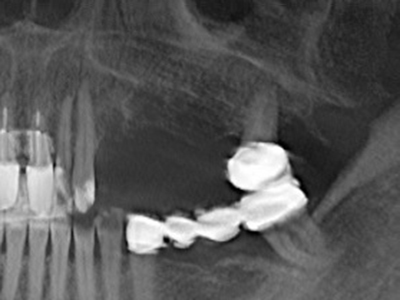

Indicazione: resezione apicale

Quando le procedure chirurgiche vengono eseguite sull'osso nelle immediate vicinanze di strutture sensibili, come vasi sanguigni o nervi, gli strumenti rotanti pongono un rischio significativo di lesione iatrogena. I dispositivi piezoelettrici possono essere utili per la preparazione delle coperture ossee e la rimozione del tessuto duro in prossimità dei nervi, in particolare per la loro esposizione dopo una lesione iatrogena, ma anche durante la lateralizzazione dei nervi per le procedure di resezione e ricostruzione o il posizionamento di impianti (figg. 17-20). Il contatto leggero tra puntina piezoelettrica e nervo non causa generalmente danni, ma se si procede senza prestare attenzione con movimenti a sega o raccordi con residui di substrati ossei possono verificarsi danni al nervo temporanei o anche permanenti. Il rischio di danno, tuttavia, è considerato sostanzialmente inferiore al rischio presente utilizzando seghe o frese (Pereira, Gealh et al. 2014).